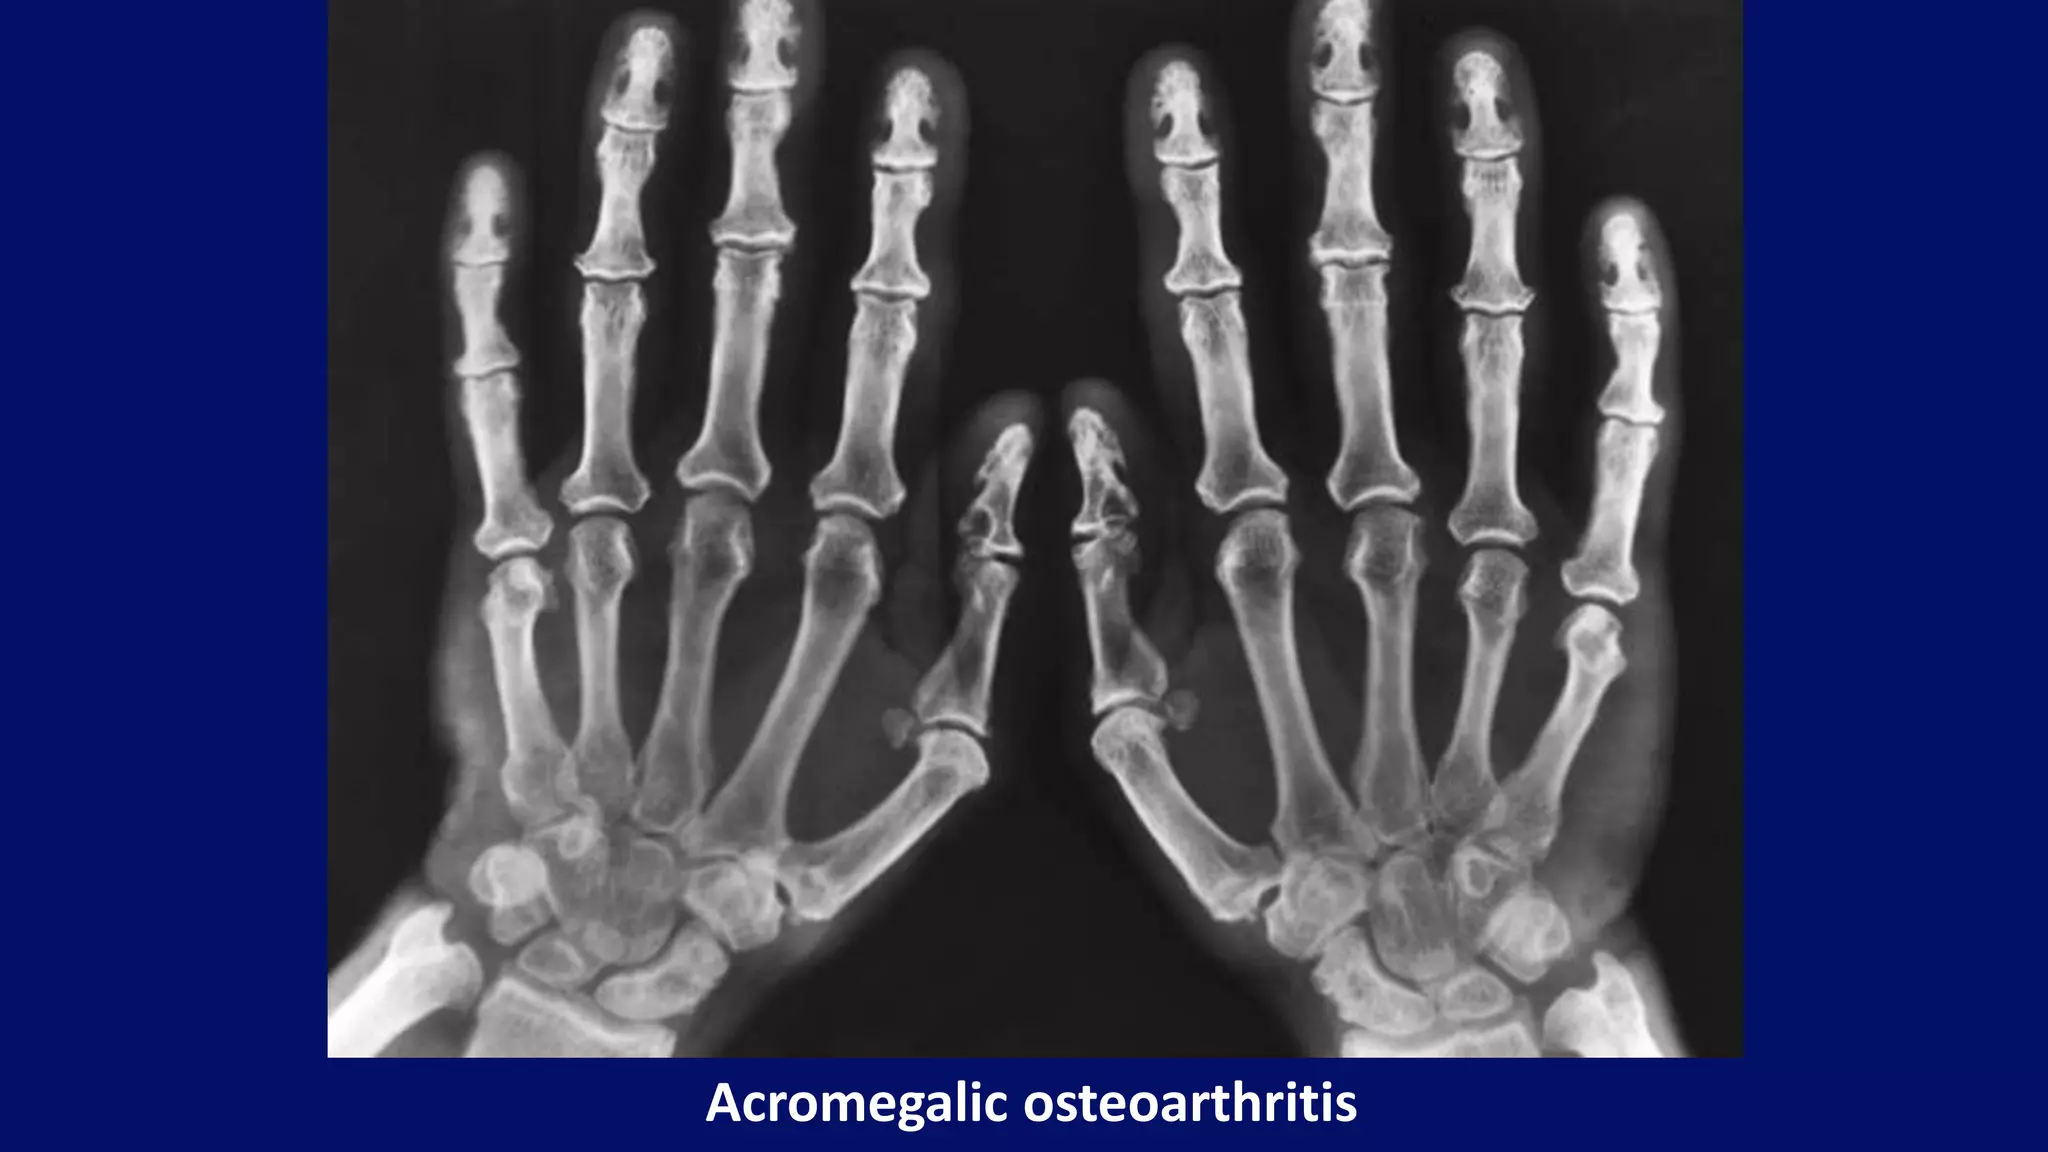

Acromegalic osteoarthritis

• #96 Dorsovolar radiograph of both hands of a 42-year-old man with acromegaly shows widening of some and narrowing of other joint spaces, enlargement of the distal tufts and the bases of terminal phalanges, and beak-like osteophytes affecting particularly the heads of the metacarpals. Note the soft tissue prominence and the large sesamoid bones at the first metacarpophalangeal joints. The sesamoid index (derived by multiplying the vertical and horizontal diameters of the sesamoid bone) is 48 in this patient; normally, it should not exceed 20 to 25.

• #97 Acromegalic arthropathy. Characteristic abnormalities in acromegalic hand include prominence of the soft tissue, enlargement of the tufts and bases of the distal phalanges, widening of the metacarpophalangeal joints, and beak-like osteophytes at the radial aspect of the metacarpal heads (metacarpal hooks). Note also markedly enlarged sesamoid bone at the first metacarpophalangeal joint.

• #98 Dorsovolar radiograph of both hands of a 42-year-old man with acromegaly shows widening of some and narrowing of other joint spaces, enlargement of the distal tufts and the bases of terminal phalanges, and beak-like osteophytes affecting particularly the heads of the metacarpals. Note the soft tissue prominence and the large sesamoid bones at the first metacarpophalangeal joints. The sesamoid index (derived by multiplying the vertical and horizontal diameters of the sesamoid bone) is 48 in this patient; normally, it should not exceed 20 to 25.